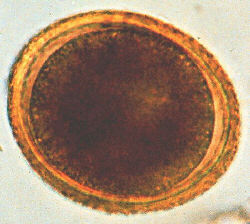

Refer to the picture above for question 1. |

1. The organisms responsible for the above appearance include: